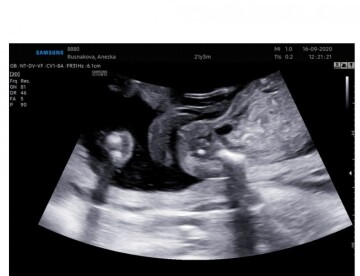

Krásný dobrý den v 18+6 jsem byla na ultrazvuku. Dostala jsem tyto fotky jsou zaměřené přímo na genitálie. Nyní už jsem 32+0 rada bych věděla co čekám za miminka přeji hezký den. Anežka. R

Dobrý den, bohužel fotografie jsou z jiného úhlu, než je ideální pro určování pohlaví. Neváhejte se zeptat Vašeho gynekologa, co na ultrazvuku vidí. Avšak ve 3. trimestru nemusí být snadné pohlaví vizualizovat. Hezký den